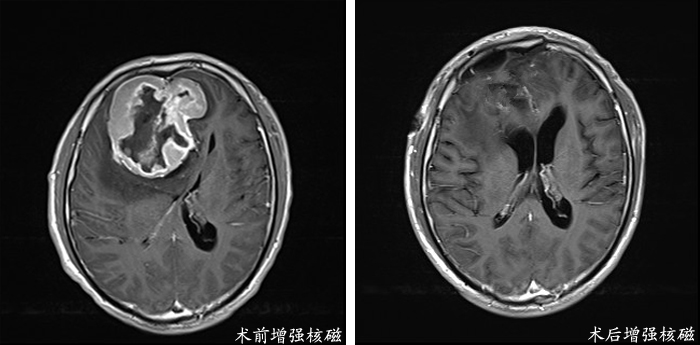

了让患者重获健康,团队经过多次认真讨论后制定了详细的疾病诊治方案,在影像科的协作下完善了手术相关的头部核磁检查。在给予患者保肝治疗并排除手术禁忌后,张洪兵主任认为根据影像检查所示患者具备手术指征,应该限期完成手术治疗。神经外科肿瘤团队勇挑重担,多名专家共同为患者设计了手术入路,预先分析了手术中可能存在的风险及处理方案。在多个科室协作下,手术顺利完成,术后李先生神经系统功能正常,复查头部核磁显示肿瘤完全切除。目前李先生已康复出院,恢复了正常的工作生活。